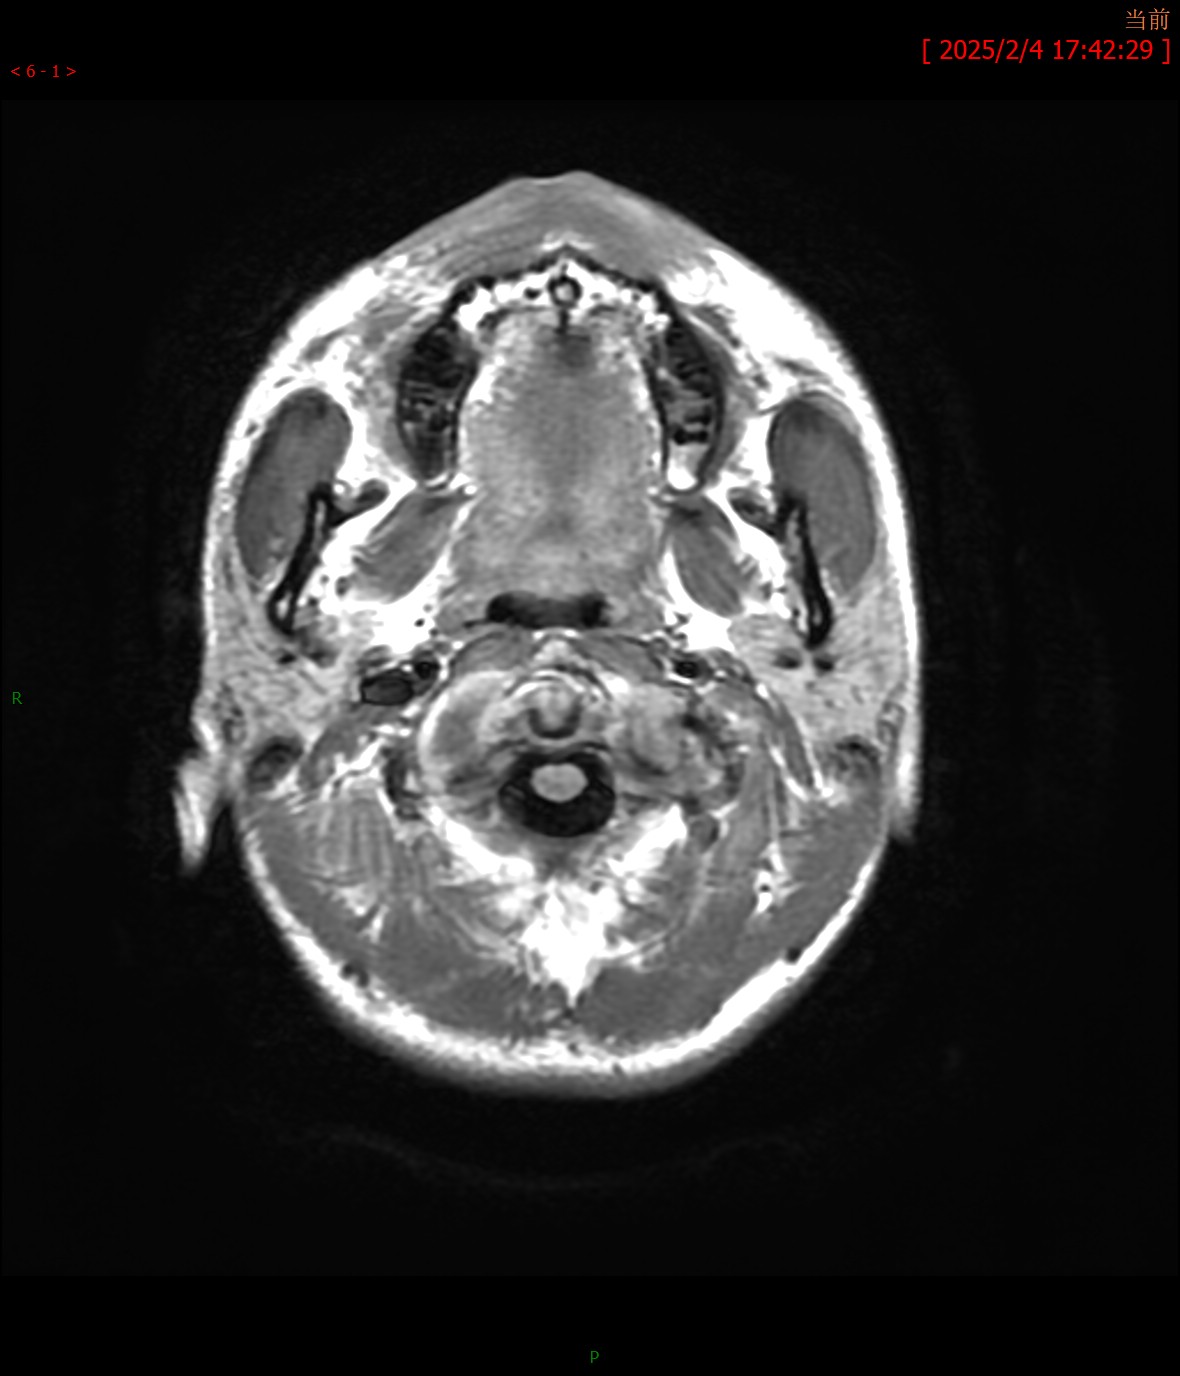

T1WI横轴位

MRA颅脑MR平扫:双侧桥臂、右侧小脑半球、延髓、桥脑、中脑、双侧豆状核、壳核可见多发斑片状稍长T1、T2信号,边界不清,病灶于T2FLAIR呈高信号,大致呈对称性分布。脑室系统轻度扩大,脑沟、脑裂增宽,中脑、小脑体积缩小,中线结构未见移位。

影像学诊断:1. 双侧桥臂、右侧小脑半球、脑干及基底核团多发异常信号伴脑萎缩改变,符合肝豆状核变性颅脑表现;2. 颅脑MRA未见明显异常。

最常见的影像表现为T2WI和T2-FLAIR图像上双侧壳核(70%)、尾状核(60%)、丘脑腹外侧(55%~60%)和中脑(50%)出现对称性高信号,这些区域反映了该病铜沉积的选择易损性特征;有时也可见脑桥(20%)、延髓(10%~15%)和小脑(10%)高信号,大脑白质(25%)和小脑白质(10%)可见局灶性或弥漫性融合状高信号。其机理主要是铜沉积于脑组织中,造成反应性水肿、神经元及胶质细胞缺失、海绵样变性和胶质增生,进而引起不可逆性的空腔和囊变。在未经治疗或治疗效果不佳时,随病程的延长,铜沉积逐渐增多,由于铜顺磁性作用,最终可形成T2WI低信号。T1WI图像上病变信号强度多样,部分病例的受累区表现为低信号,而部分病例则表现为高信号,类似慢性肝性脑病,反映了铜的顺磁性效应。对称性基底节异常信号同时伴有脑干病灶是该病的影像特征。当病变发展到一定程度时,随着神经元及胶质细胞广泛坏死、变性,常出现基底核团及脑干萎缩表现,甚至可出现全脑萎缩。